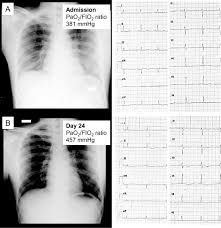

Imaging In Covid 19 Related Myocardial Injury Springerlink from media.springernature.com Am j med case rep. 5 476 просмотров 5,4 тыс. Journal of the american college of cardiology vol. Symptoms can include shortness of breath, chest pain, decreased ability to exercise, and an irregular heartbeat. Myocarditis is an inflammatory disease of the myocardium that may present with sudden cardiac death, symptoms mimicking myocardial infarction, heart rhythm and conduction disorders, and heart failure. If true, this could, in part, explain some of the observed cardiac injury and arrhythmias in. Indirect myocardial injury, myocardial inflammation or myocarditis? Myocarditis is an inflammation of the heart muscle (myocardium).

Cardiovascular Manifestations And Treatment Considerations In Covid 19 Heart from heart.bmj.com Myocarditis is an inflammatory disease of the myocardium that may present with sudden cardiac death, symptoms mimicking myocardial infarction, heart rhythm and conduction disorders, and heart failure. A position statement of the european society of cardiology working group on myocardial and pericardial diseases. Myocarditis is an inflammation of the heart muscle (myocardium). Indirect myocardial injury, myocardial inflammation or myocarditis? Republic of cyprus ministry of health. If true, this could, in part, explain some of the observed cardiac injury and arrhythmias in. 5 476 просмотров 5,4 тыс. Symptoms can include shortness of breath, chest pain, decreased ability to exercise, and an irregular heartbeat.